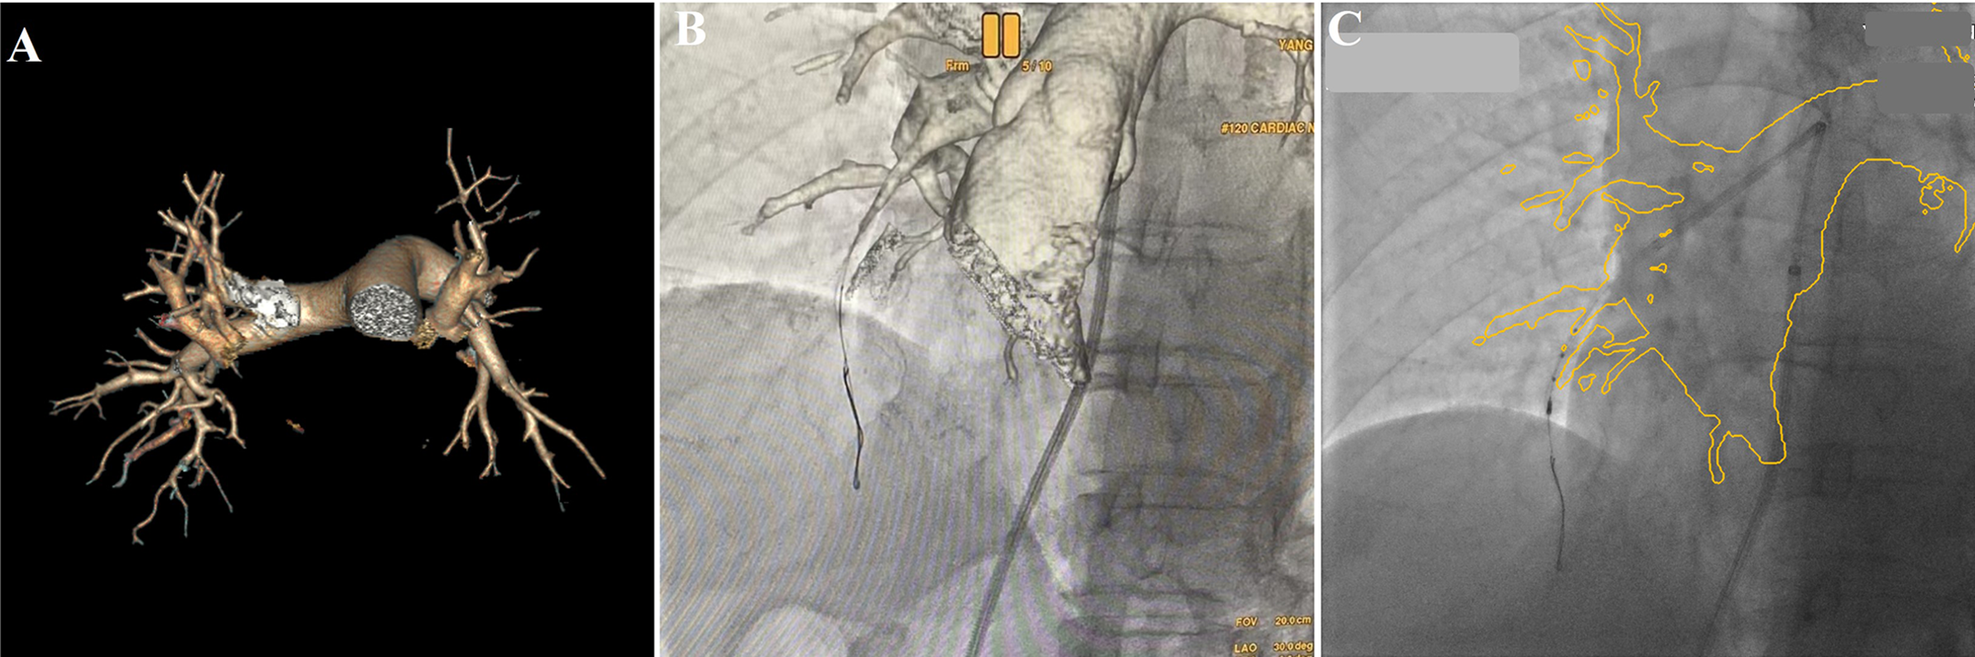

Six months later, the patient was re-admitted for re-examination, and right heart catheterization was performed which showed mPAP of 28 mmHg, mPAWP of 8 mmHg, CO of 5.1 L/min and PVR of 3.92 Wood units. As the use of an iodine contrast agent was contraindicated, BPA procedure was performed by the following methods: the patient's previous multidetector computed tomography images were transmitted back to the AW4.7 workstation (GE Healthcare), and the AutoBoneXpress function was selected to manually extract a part of trachea and spine respectively, and improve the following registration precision and speed. At the same time, virtual reality reconstruction of the pulmonary artery vascular structure was performed and marked with the image fusion software Value Assist 2; the spine and trachea were registered, and the view switched to the vascular image to start intraoperative real-time navigation (IGS530, GE Healthcare) for performing BPA (Figure 1). It can guide the direction of the guidewire within the pulmonary artery without contrast agent assisted tracing, ensuring more efficient navigation through narrowed areas of the pulmonary artery. Additionally, it also provides real-time guidance on the positioning of the guidewire and balloon during interventional procedures.

Figure 1

Virtual reality reconstruction of the patient's pulmonary artery based on previous pulmonary artery CTA image (A), real-time image fusion navigation guided the direction of the guidewire via pulmonary artery to A7 (B, Virtual reality), and guided the IUVS into A8a (C, outline volume-rendered) during BPA procedure.